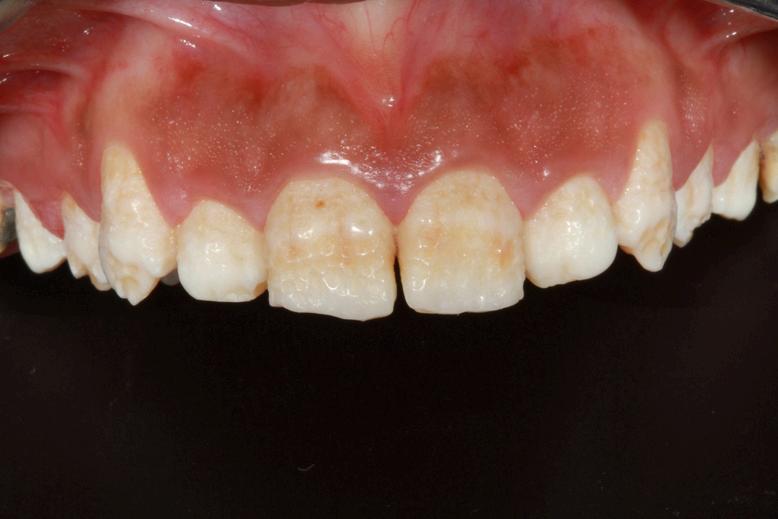

Este es un defecto cuantitativo del esmalte, es decir, existe buena mineralización pero cantidad disminuida de este tejido en la zona del defecto. Existe pérdida de la continuidad del tejido, con posible exposicion de dentina y se presenta con bordes definidos, redondeados y generalmente son de color blanco o crema

La diferencia con la Hipomineralización molar incisivo está en su estructura, origen y color No tiende a presentar colores tan intensos y su aparición es aleatoria e idiopática en la mayoría de los casos Se le debe prestar mucha atención ya que puede desencadenar situaciones graves por decisiones incorrectas en los tratamientos, mal uso de los materiales odontólogicos e identificación tardía.

Si bien existe la hipoplasia medicamentosa, no se tiene claro cuales medicamentos pueden intervenir en la formación del esmalte, siendo la placenta un filtro muy efectivo para la mayoría de ellos, es poco frecuente que el esmalte de los dientes primarios se encuentre involucrado en estas lesiones. Se puede vincular la ingesta de larga data y la posología de los medicamentos al defecto, pero suele relacionarse más a la enfermedad directamente como la causa de ciertas lesiones hipoplásicas.